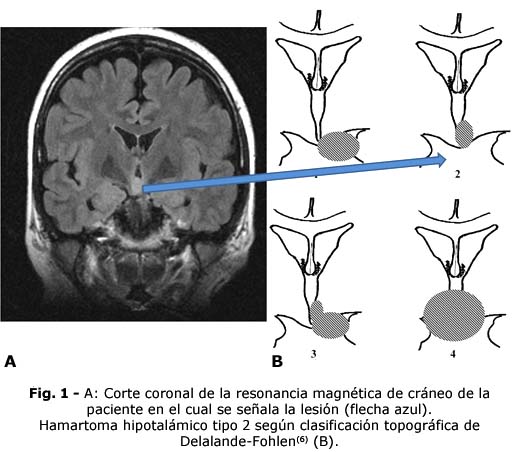

A los 36 años luego de haber cumplido exitosamente misiones internacionalistas y varias responsabilidades laborales, refiere disminución de memoria verbal, de habilidades comunicativas y llanto fácil. Se ingresa en el Instituto de Neurología y Neurocirugía (INN) donde se diagnostica una epilepsia farmacorresistente secundaria a hamartoma hipotalámico (Fig. 1).

6. Delalande O, Fohlen M. Disconnecting surgical treatment of hypothalamic hamartoma in children and adults with refractory epilepsy and proposal of a new classification [Internet]. Neurol Med Chir (Tokyo). 2003; 43(2):61-8. DOI: 10.2176/nmc.43.61. PMID: 12627881.